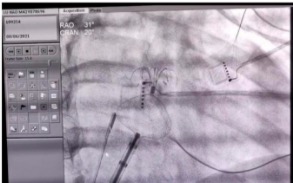

牵拉测试左心耳封堵器稳定性

左心耳封堵器+房间隔缺损封堵器